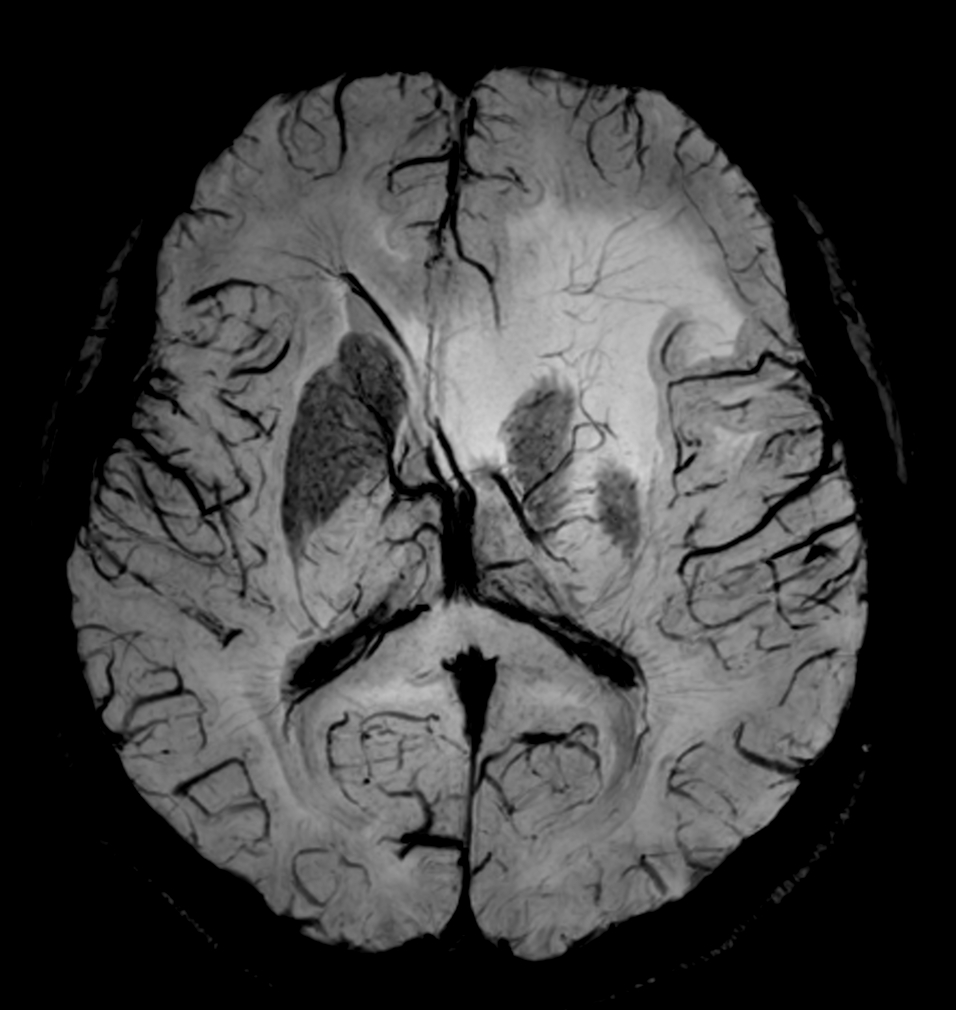

SWIp (minIP)